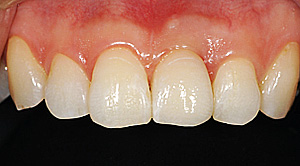

- 右上1を抜歯しソケットプリザーベーション(抜歯したまま放置すると骨が高度に吸収してしまうため、それを予防するための処置)を行い、隣在歯と骨レベルを合わせたのちにインプラント埋入を行った。

インプラントは理想的な状態に仕上がり、他の歯のクラウンも美しく調和することができた。患者さんも非常に満足度がたかかった。